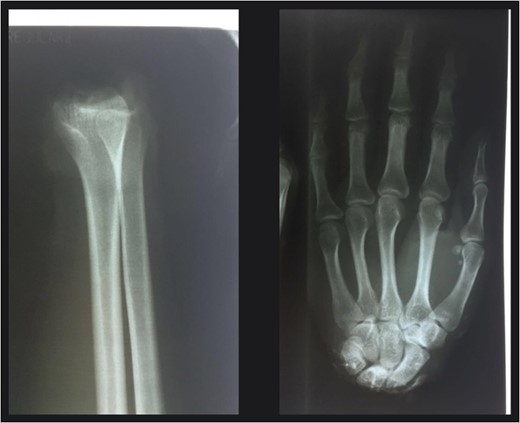

Patient was evaluated at entry to the emergency room, conscious and oriented in time, space and person, 15 points in Glasgow scale, vital signs: P/A: 110/70 mmHg, FC: 82 min−1, T: 37.1 °C and 20 breaths per minute, presented a superficial laceration in right side of face, malar region, 8 cm in longitude, transverse, at the level of the left superior extremity; did not present active bleeding of the stump due to blood vessel coagulation, patient is sent to X rays, for AP and lateral projection of the hand and stump (Fig. 2).